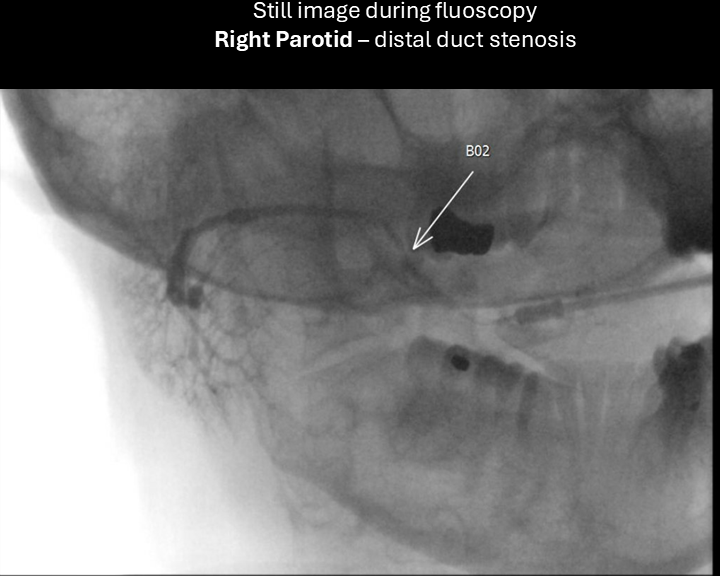

Sialogram:

Performed with 24-gauge angiocatheter - following sialogram, further dilation of duct with 22-gauge angiocatheter over 0.015-inch guidewire - unable to advance 20-gauge catheter.

right parotid sialogram 2

right sialogram 3

right sialogram 4